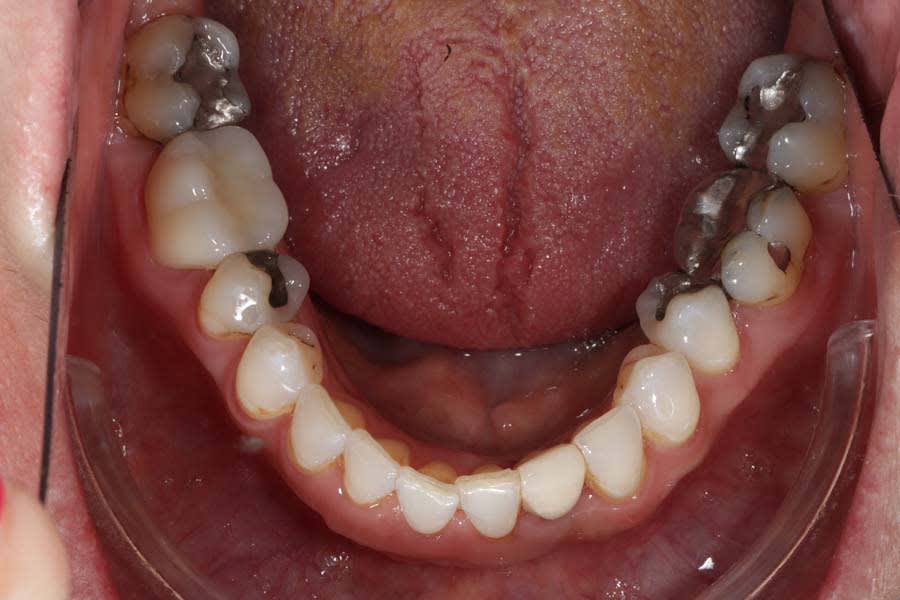

Biomechanical: No active caries or xerostomia was noted, but the fractured amalgam on tooth No. 30 prompted urgent treatment. Large restorations on teeth Nos. 2, 3, 12 through 15, 18 through 20, and 31, along with large Class III composites on teeth Nos. 6 through 9, indicated structural compromises. Root canal treatment on teeth Nos. 4 and 10 (apicoectomy and post-and-core [FlexiPost®, Essential Dental Systems, edsdental.com]) and marginal fractures on teeth Nos. 5 and 12 put these teeth at even further risk. Despite the lack of symptoms, future pulpal pathology was a risk for many of the patient’s structurally compromised teeth (Figure 4 and Figure 5).

Posterior uprighting: Posterior teeth were slightly uprighted to align occlusal forces, open the vertical dimension of occlusion, and widen the buccal corridors. This increase in intraoral space created more room for the patient’s tongue, decreasing airway concerns (Figure 10 and Figure 11).